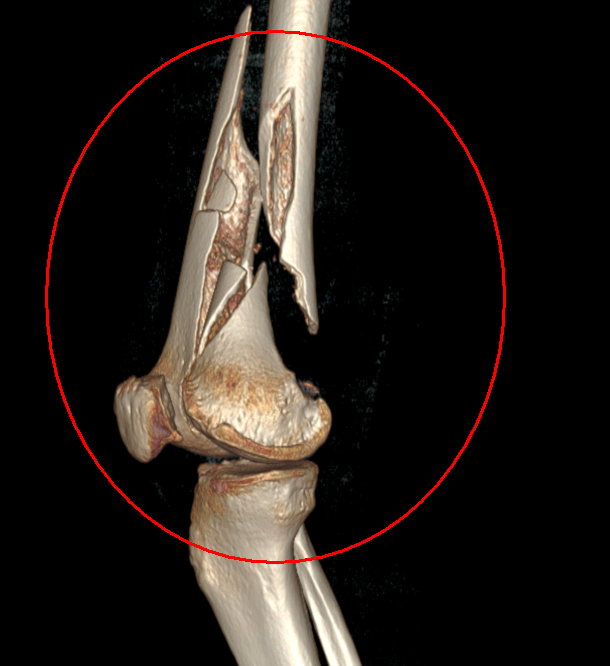

治療前88歲高齡患者,摔傷致左髖部疼痛伴活動受限2小時入院,急診拍片顯示:左側股骨轉子間骨折治療中完善術前檢查,多學科會診,入院第三天行椎管麻醉下左側股骨近端髓內釘內固定術(PFNA)治療后治療后7天術后疼痛緩解,患者可扶助行器行走